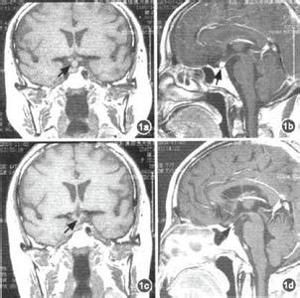

头颅平片一般正常,不过,垂体明显增大的病人头颅平片也可有蝶鞍增大的表现,CT和MRI对诊断有重要的意义,本病垂体CT和MRI的表现有:垂体增大或垂体占位(可伴鞍上扩展),垂体柄增粗,空鞍,垂体有囊性病变,垂体增大或垂体占位是最常见的影像学改变,约见于90%的病人,鞍上扩展亦相当常见(见于60%~70%的病人),本病垂体多呈弥漫性增大,这一点与垂体腺瘤不同,对鉴别诊断有一定的意义,垂体柄增粗则较少见,多发生于神经垂体和漏斗受累的病人,空鞍和垂体囊性病变则更为少见,久病者可有垂体萎缩但蝶鞍仍扩大,少数病人垂体CT和MRI检查可无异常发现。

1.垂体腺瘤: 分泌性垂体腺瘤多有某种腺垂体激素过多的表现,借此可与本病鉴别,分泌性垂体腺瘤中的PRL瘤易与本病混淆,但PRL瘤病人血PRL升高较本病更为明显,无功能垂体腺瘤无垂体激素过多的症状(PRL可轻至中度升高),表现为腺垂体功能减退,与本病很相似,但无功能垂体腺瘤的占位症状(头痛,视力减退,视野缺损等)较本病常见且显著,此外,无功能垂体腺瘤引起的腺垂体功能减退以促性腺激素减少最先出现且最为常见,ACTH和TSH减少出现较晚且较少见;淋巴细胞性垂体炎引起的垂体功能减退则以ACTH和TSH减少较先出现,且最为常见,促性腺激素减少出现较晚,且相对少见一些,影像学检查对垂体腺瘤和本病的鉴别有很大价值:在CT和MRI上,垂体腺瘤病人垂体为局灶性增大,本病则为弥漫性,均质性增大;垂体腺瘤可有蝶鞍骨质的破坏,本病一般没有。